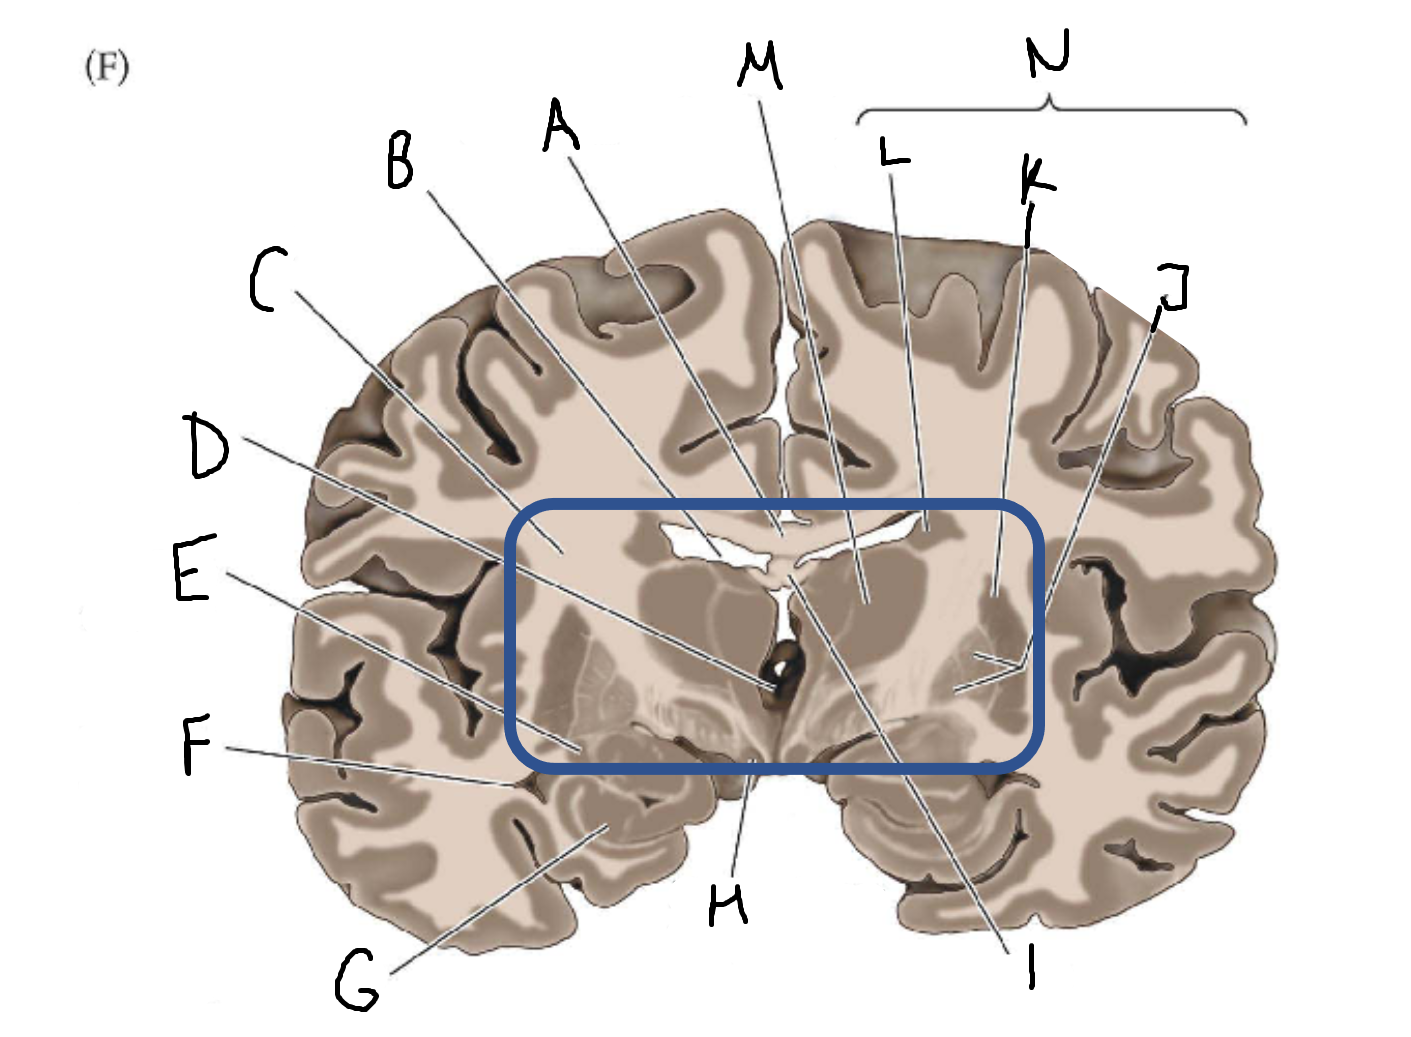

A

corpus callosum

B

lateral ventricle

C

internal capsule

D

third ventricle

E

tail of caudate nucleus

F

lateral ventricle

G

hippocampus

H

mammillary body

I

fornix

J

globus pallidus

K

putamen

L

caudate

M

thalamus

N

basal ganglia